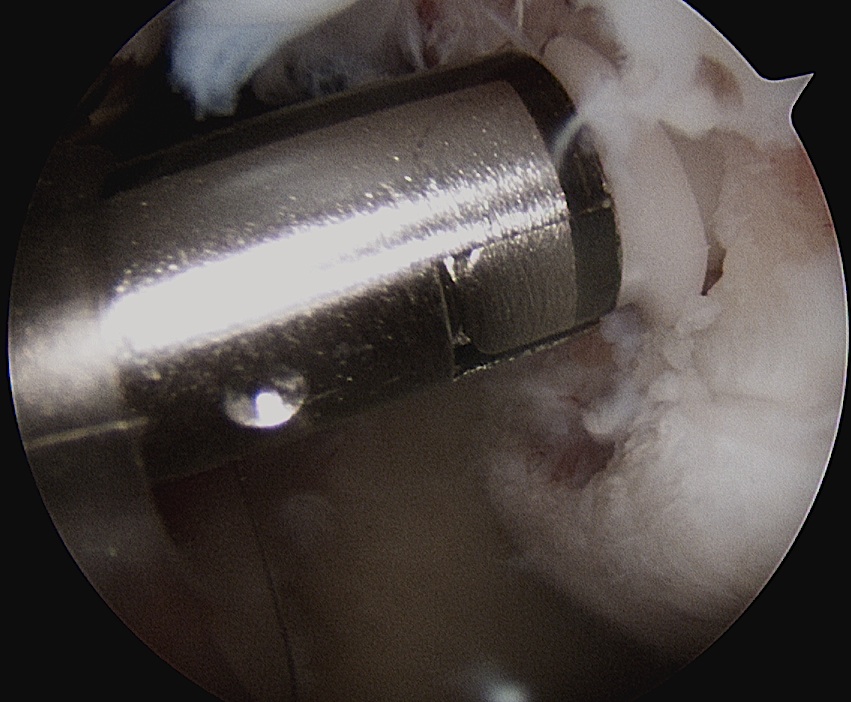

- insert anchors at medial aspect of defect

Anchor insertion into Hill Sachs lesion